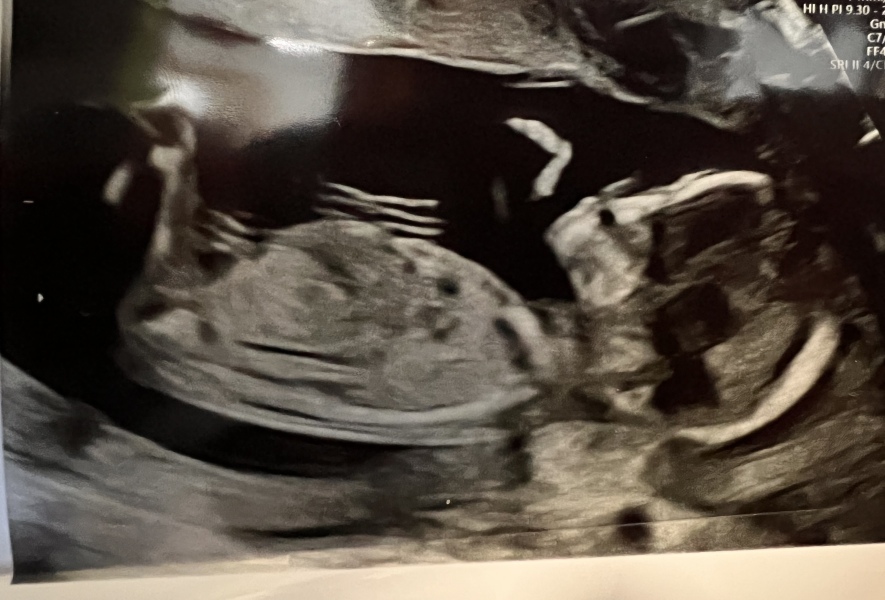

scan day! hooray!

aside from that, what a glorious day of wonderful wriggly baby visuals. They didn’t do her heartbeat which surprised me but we saw lots of her getting her groove on in there. She’s definitely my child. She can move more that her father already 😁

@Pommy1 lovely scan pic and glad to hear that you were seen.

@Pommy1 that's a lovely scan photo! xx

@Pommy1 congratulations! Lovely scan photo 🎀💖

@Pommy1 glad you got your scan and lovely picture 🥰

@Pommy1 gorgeous scan pic! 😍

@Pommy1 lovely scan photo, congrats!